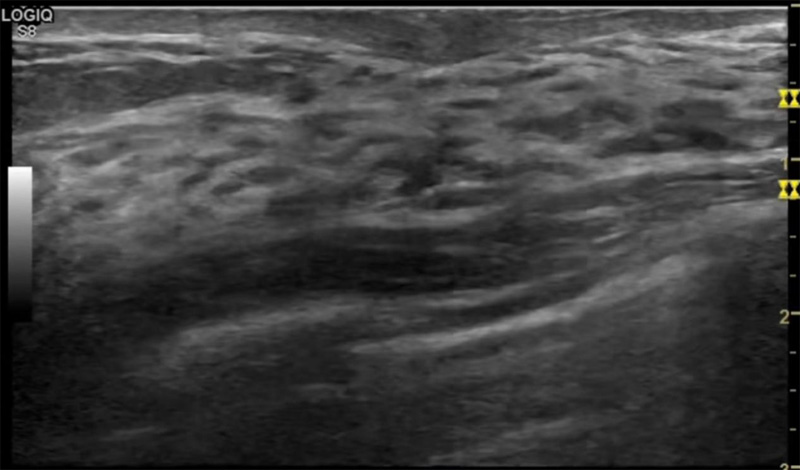

乳房胀痛,触摸疼痛,手摸起来感觉有肿块。这个是什么问题呢?医生诊断一般是乳腺增生。那么在乳腺超声设备检查后,报告单却显示双乳未见明显占位性病变。乳腺增生是很多女性,特别是育龄期女性都有的经历、到底乳腺增生症状有哪些?会给我们带来怎样的影响呢?乳腺增生不是肿瘤跟炎症。乳腺组织增生及退行性变跟内分泌功能紊乱有关系。正常的生理改变。还有乳腺病,良性乳腺结构不良等名称。

乳腺增生有什么症状,病因?比较典型的就是乳房疼痛,特别是经前症状比较重,经后就有所缓解。有时候还能碰到乳房硬块。根据经期的变化而变化硬度大小都有变。乳腺在内分泌激素,伴随月经周期有增生问题。内分泌激素代谢失衡,雌激素水平增高,出现乳腺组织增生过度,增生组织不退的情况下,就会有乳腺增生症状。这个不会增加乳腺癌的风险。所以不用紧张的。不过乳腺癌的病人都会有乳腺增生。所以乳腺增长有没症状,都需要进行常规的体检。